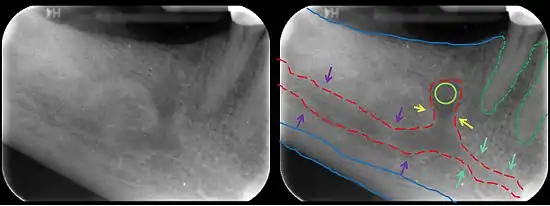

El canal mandibular está bastante cerca de los ápices del segundo molar en el 50% de las radiografías. En el 40%, el canal está alejado de los ápices de la raíz, y en sólo el 10% de las radiografías los ápices de la raíz parecían penetrar en el canal.

En la terapia del canal radicular del segundo molar se debe tener cuidado de no extender demasiado el escariador o los materiales de relleno del canal radicular porque hay un posible riesgo de lesión del nervio alveolar inferior[2]